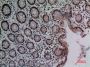

Applications WB, IF, IHC, ELISA

IHC-P 1:100-300